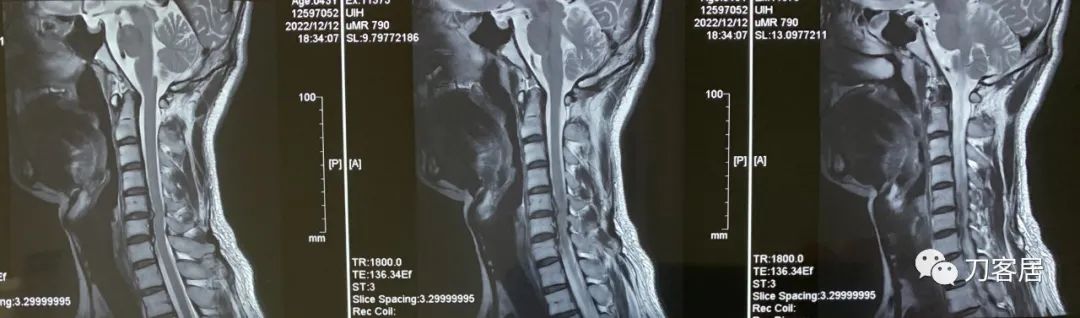

现病史:自2022年6月始,右颈肩痛,曾就诊于上海华山医院(应该是2022年12月12日,病历我拍照的时候忘了拍就诊日期了),磁共振检查提示颈椎病,建议手术治疗。患者因是在上海打工,所以没做手术。现症状已较发作初始减轻。遂来我院就诊。

自带颈椎MRI提示颈5-7椎间盘突出。

图1. 20221212上海华山医院颈椎MRI01,可见颈5-7椎间盘突出,在第三张图中,突出较大,对于脊髓还是有压迫,椎管有狭窄。